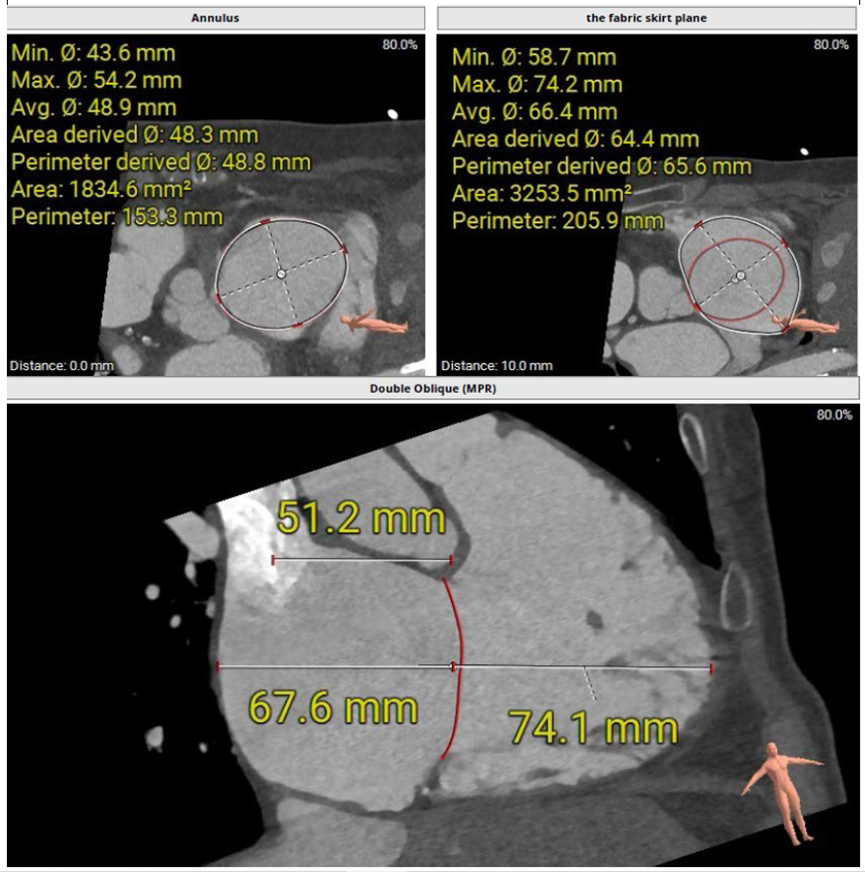

術(shù)前CT評估三尖瓣瓣環(huán)大小